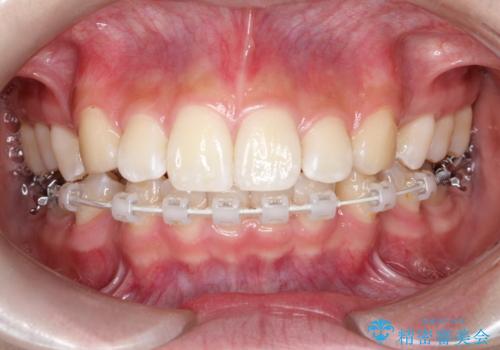

- ハーフリンガル

- 3年1ヶ月

- 出っ歯を治したいとのことで来院されました。

目立たない装置が希望とのことでハーフリンガルで治療をすることとしました。